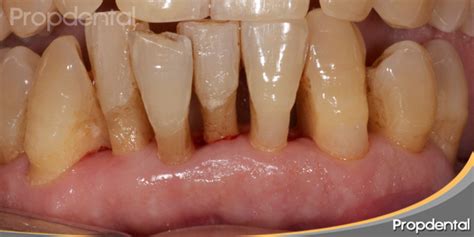

Como mencionamos, la periodontitis es una de las causas de pérdida de hueso de la mandíbula, asistir regularmente a las consultas con tu dentista te puede ayudar a prevenir problemas mayores asociados a esta enfermedad.

Pérdida de hueso por periodontitis avanzada.

Estos factores pueden hacer que tu hueso dental no tenga la suficiente altura, ancho y densidad. La pérdida de hueso en la mandíbula también puede darse por periodontitis.